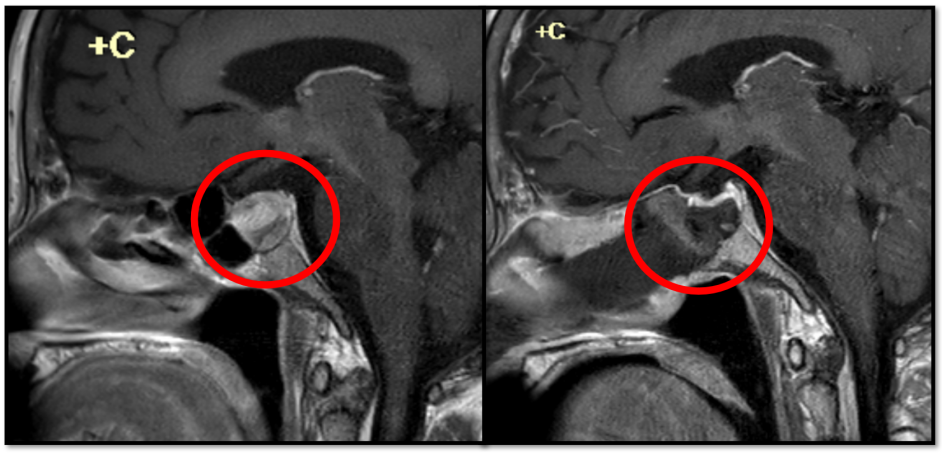

通过相关检查,医生明确了病因:患者鞍区占位(垂体腺瘤)伴出血导致内分泌功能障碍,进而出现的一系列行为异常的症状。该院神经外科手术治疗团队很快为其制定了相应的手术治疗方案,肿瘤完全切除。出院时阿婆完全恢复了正常状态,露出了久违的笑容。

前往南医三院就诊后,该院神经外科医生结合患者存在多器官症状以及辅助检查结果,很快安排了院内多学科会诊,综合多学科专家意见,立即进行了“颅内岩下窦采血”检查,最终得出了确定诊断:郑女士患上了促肾上腺皮质激素型垂体腺瘤。

经鼻内镜手术治疗,肿瘤完整切除。术后患者每日以肉眼可见的速度消肿,居高不下的血压也逐日下降,患者和家属悬着的心也终于放了下来。